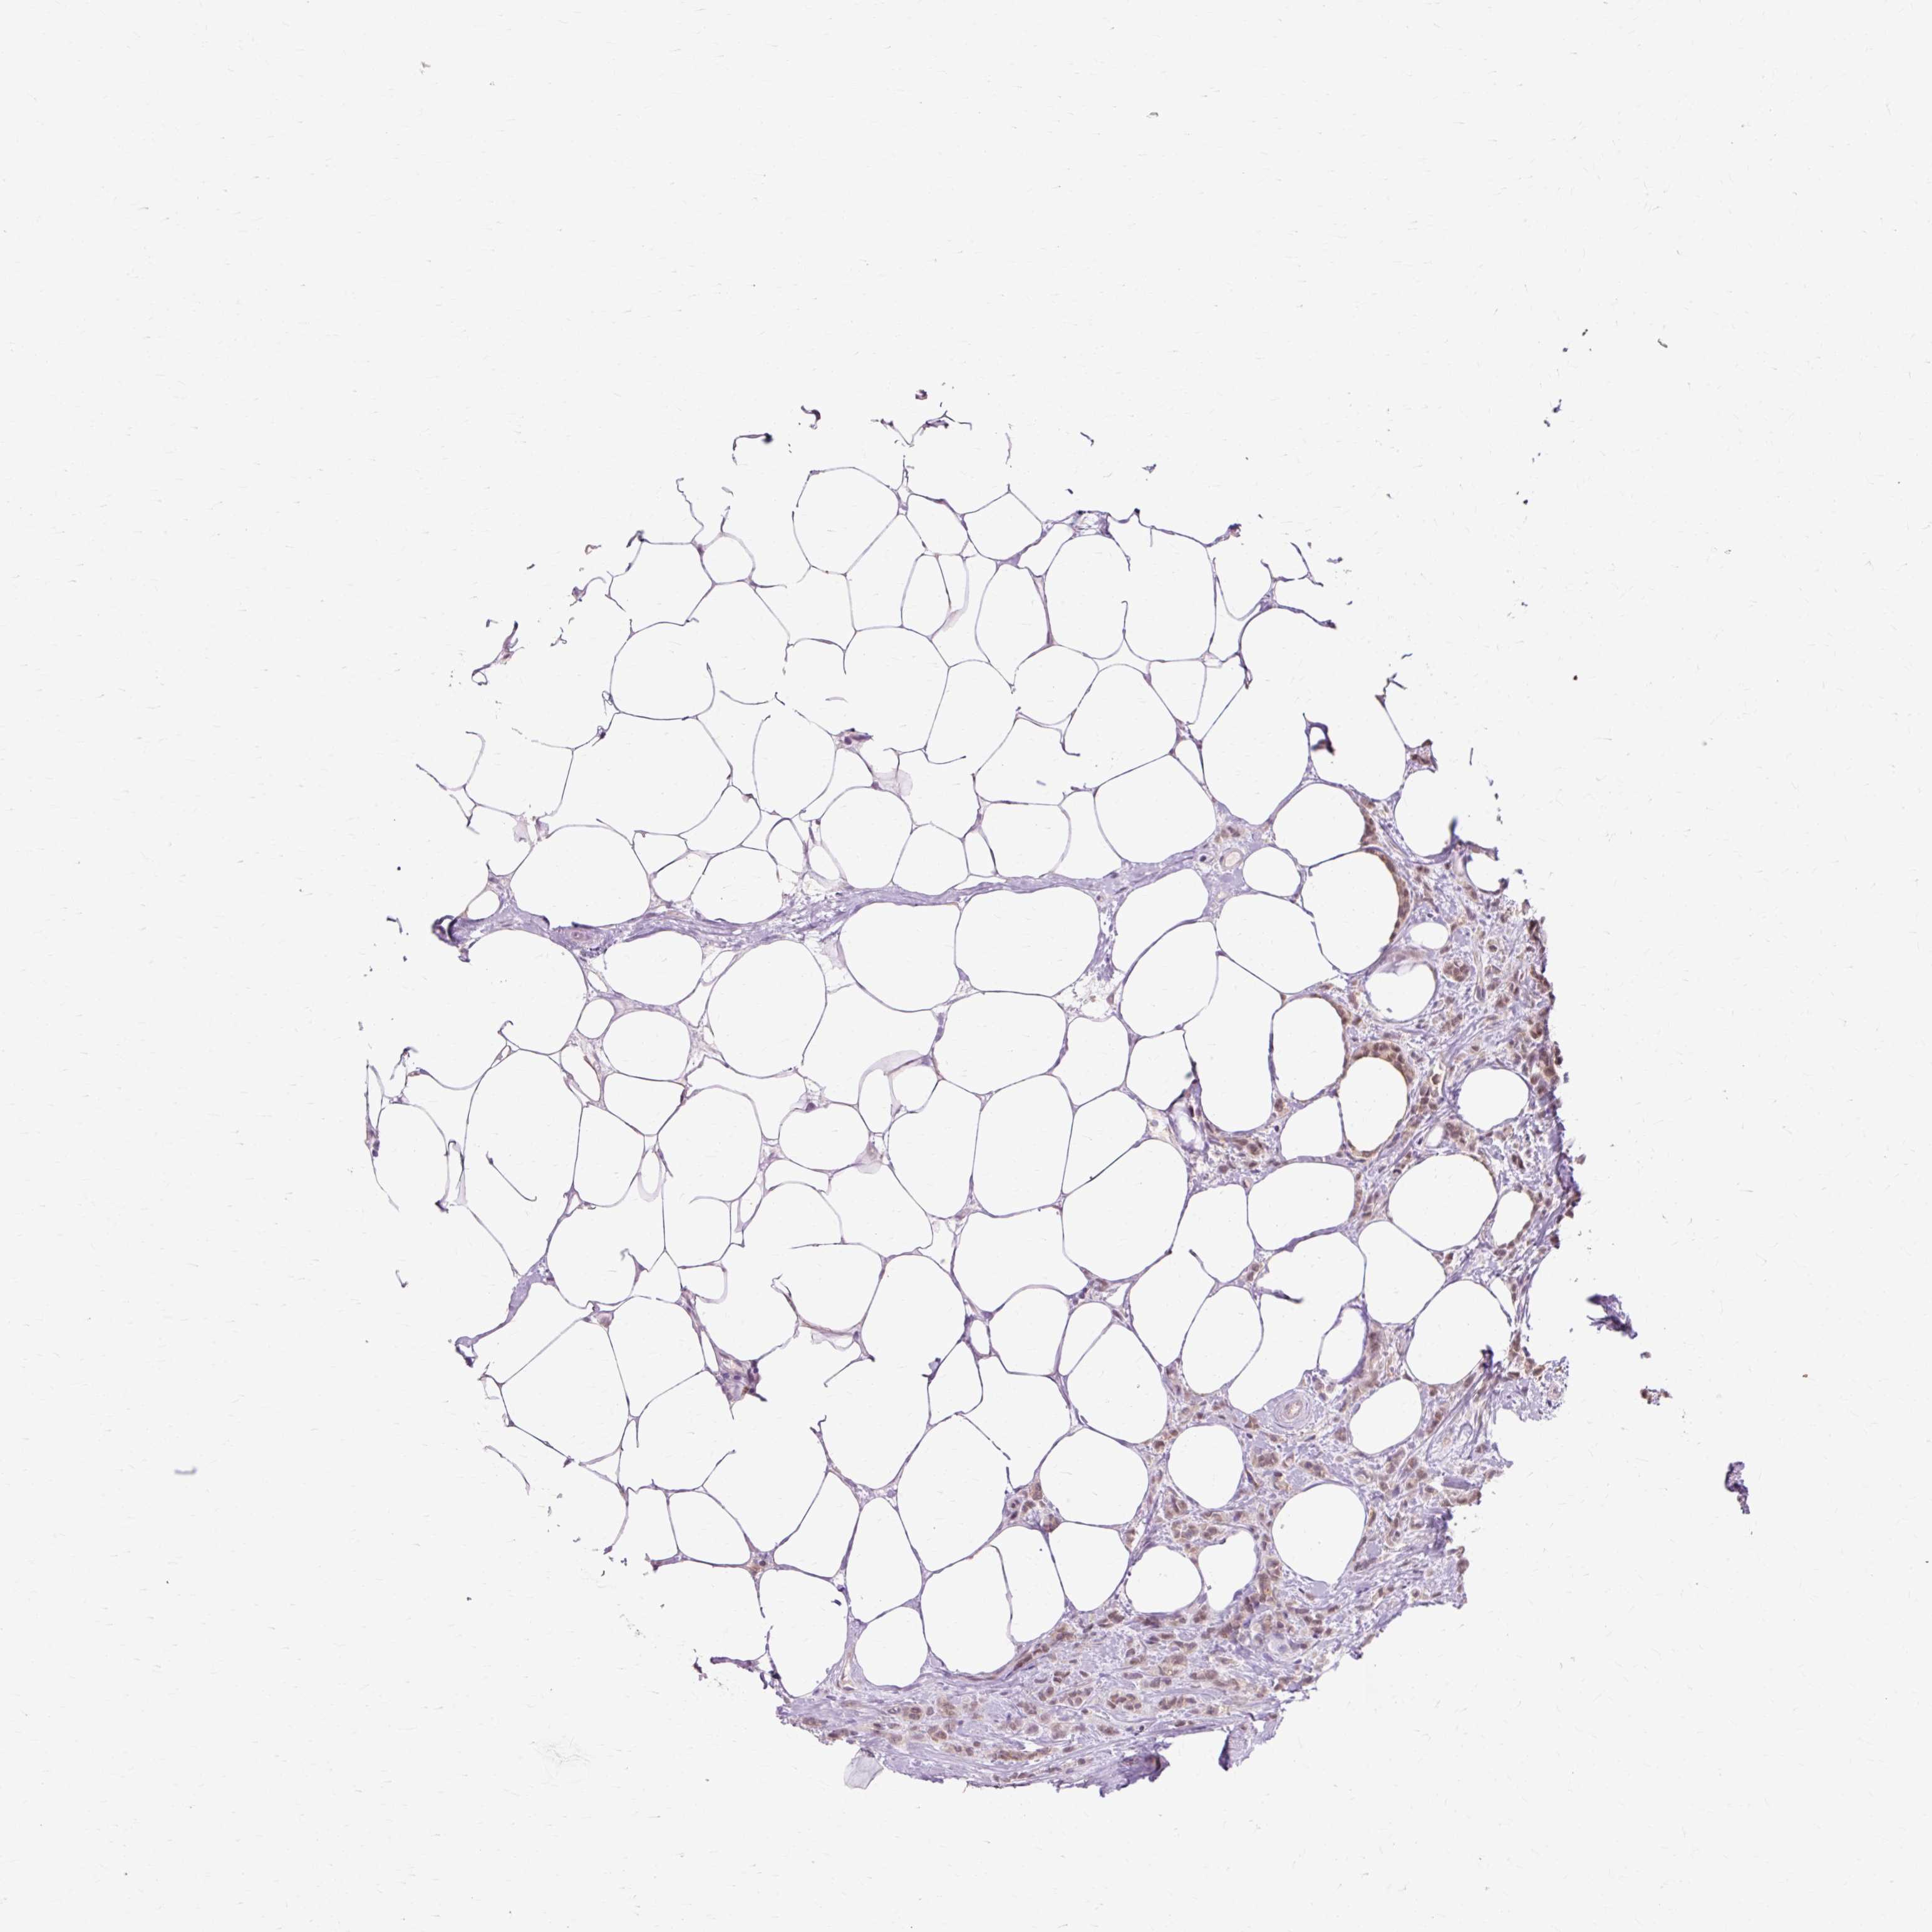

CANCER BREAST CANCER Show tissue menu

BRCA TCGA BRCA VALIDATION PROTEIN EXPRESSION

ANTIBODIES

AND

VALIDATION